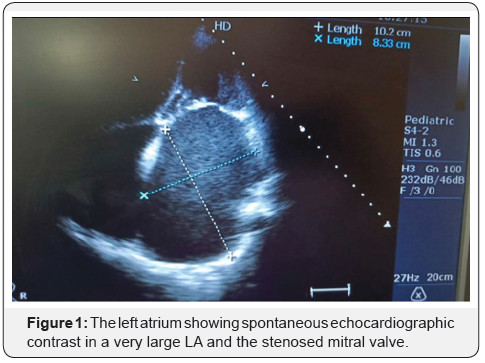

A female aged 86 years with a weight of 30 kgs and a height of 141cm (BMI =15.1) was diagnosed with severe MS (MVA =1.0/1.1cm2, MVG 20/14 mmhg) and (MVS/Wilkins) 3/2/2/3 score with mild mitral regurgitation (MR), with a very large (10.3 cms) left atrium (LA) and grade III spontaneous echocardiographic contrast (SEC) (Figure 1). The normal mitral valve area (MVA) is about 4-6 cm. When this area becomes less than 2 cm the stenosis starts becoming significant. A valve area below 1 cm makes it a critical MS. The pressure difference between the left atrial pressure and the end-diastolic pressure of the left ventricle is the gradient across the mitral valve. This gradient increases with an increase in the heart rate because diastole is shortened than the systole [3]. Wilkins scoring system evaluates leaflet thickening, mobility, calcification, and sub valvular involvement on a scale of 0-4 [4]. SEC indicates blood stasis in cardiac chambers and major vessels and is a known precursor of thrombus formation [5]. The patient had recurrent admission for acute decompensation, later she had paroxysmal atrial fibrillation.